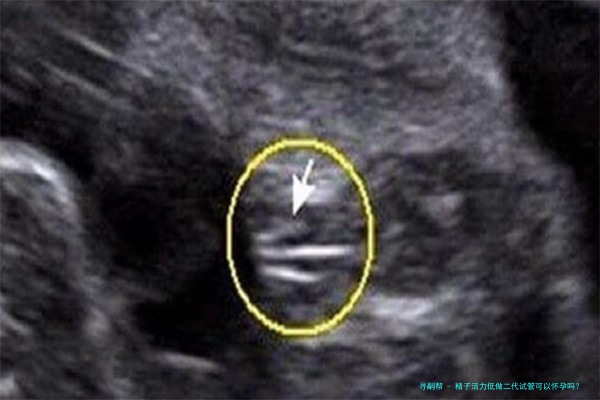

四、ICSI操作:将筛选出的精子通过显微操作技术直接注入卵子里面。